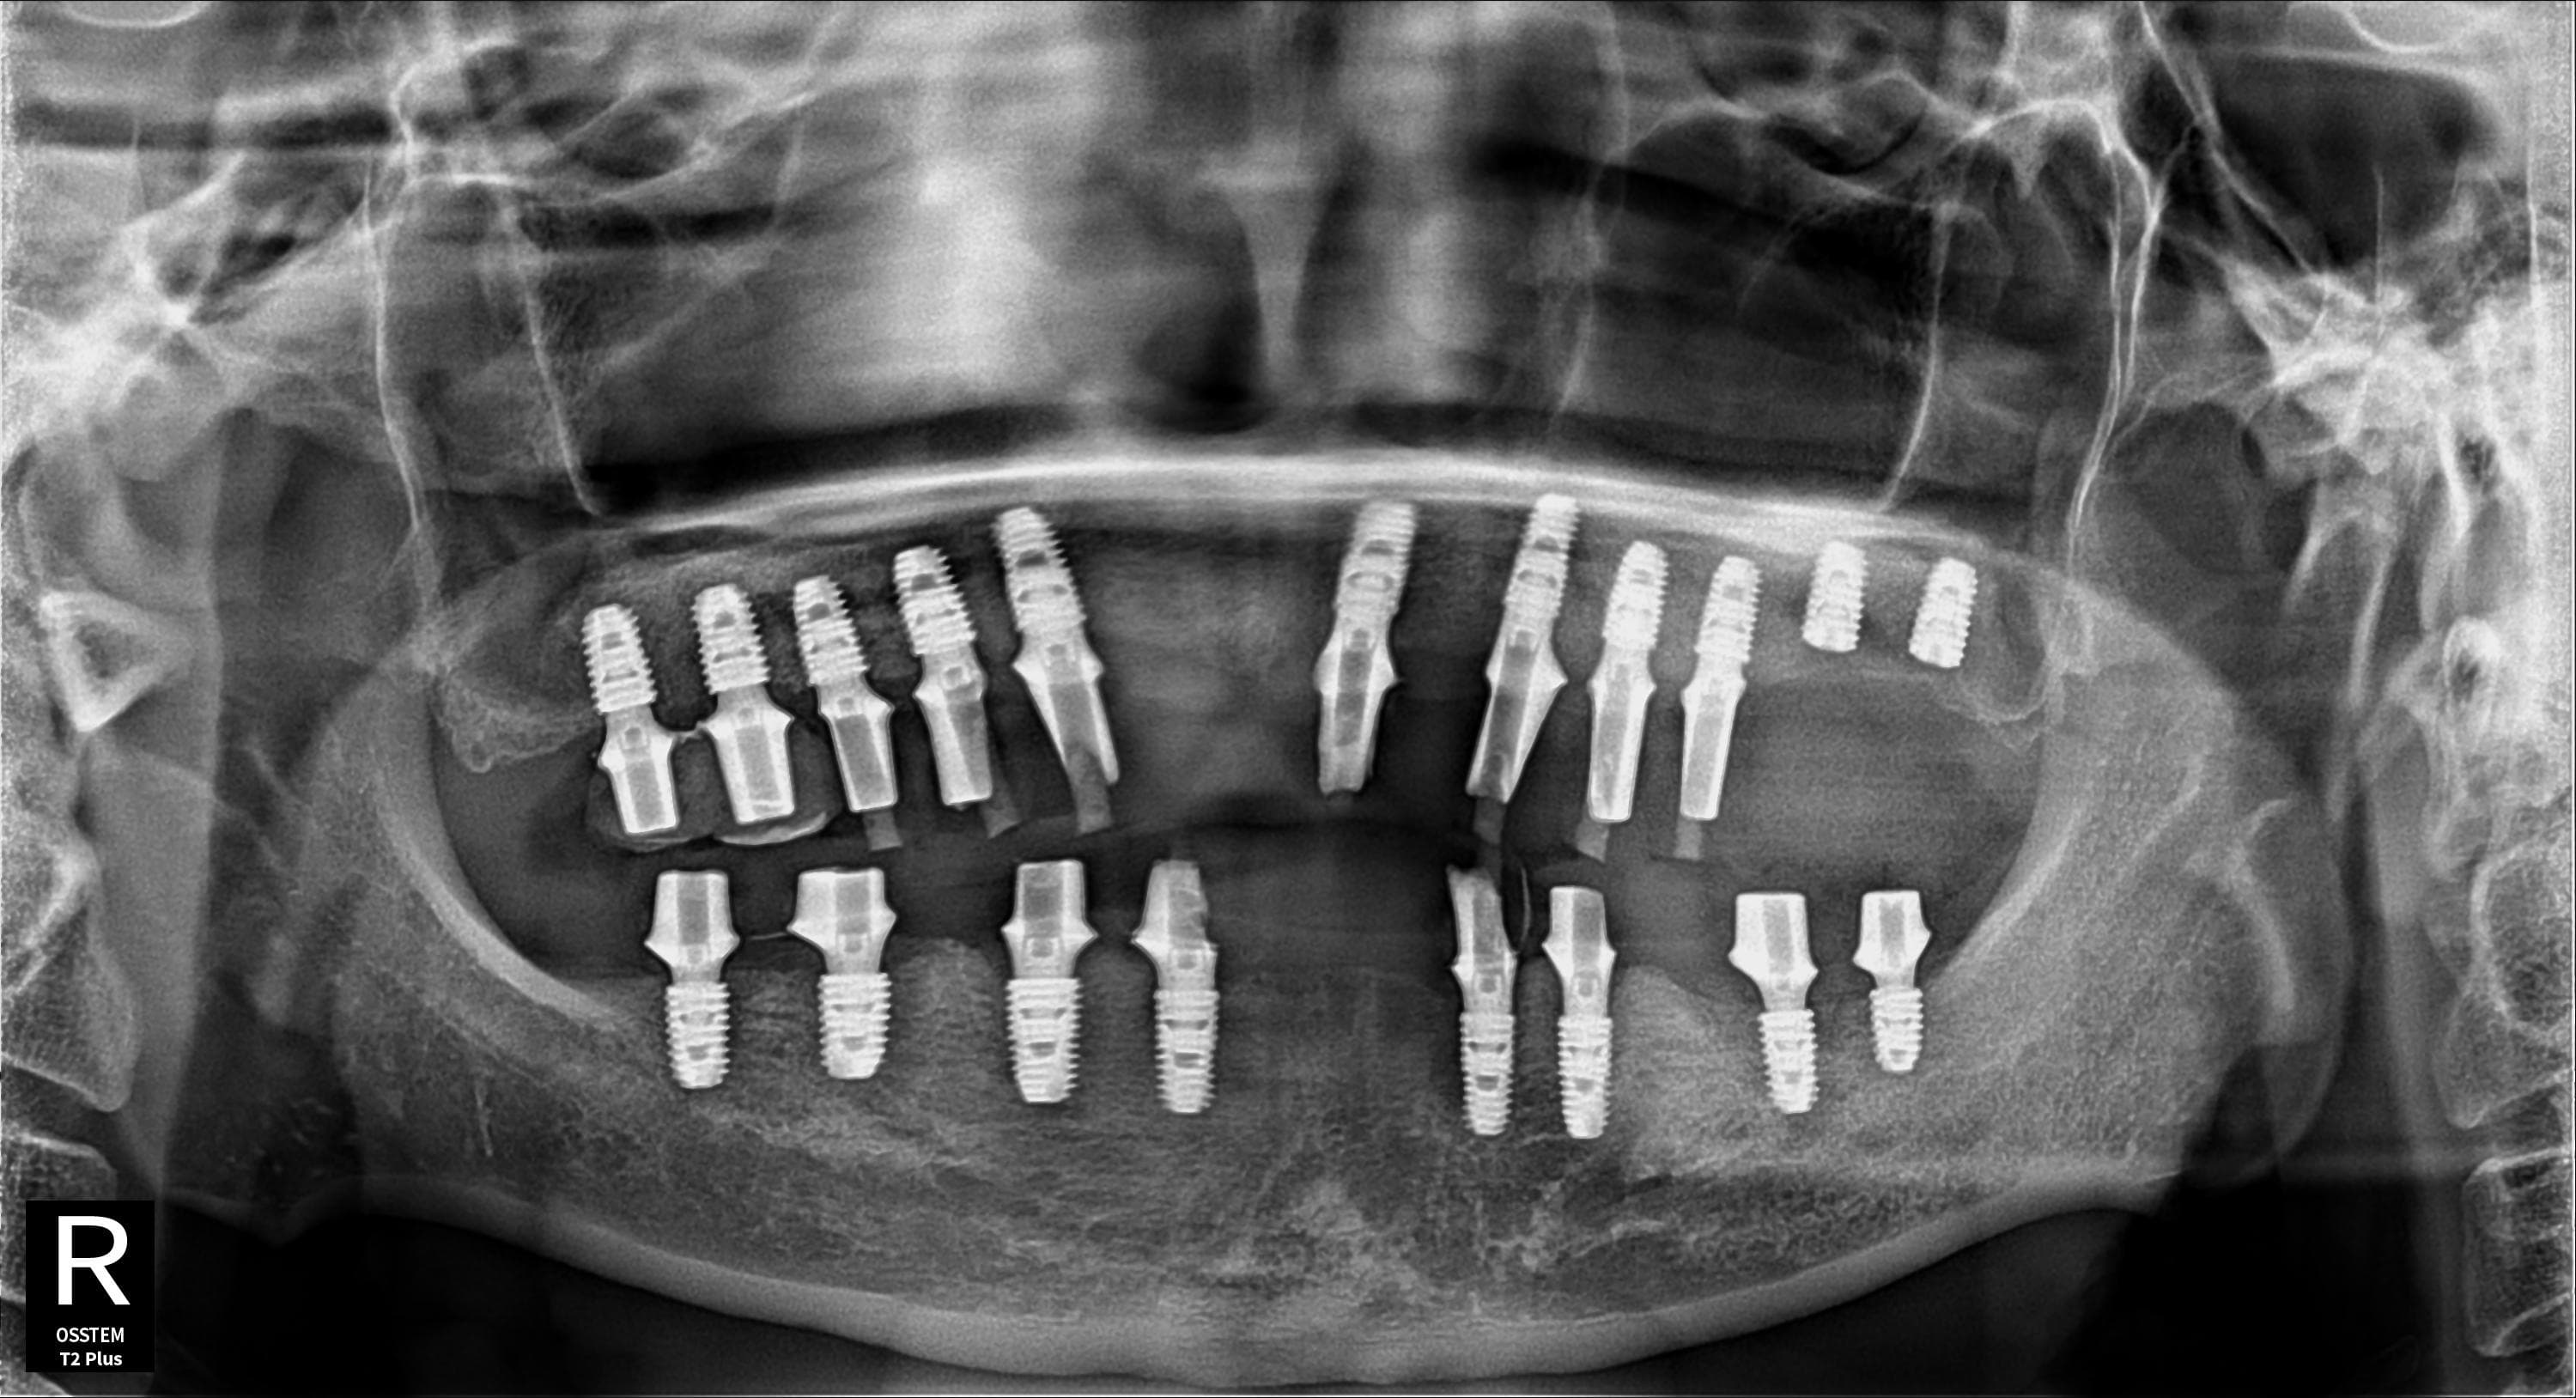

박●● · 남성

전악 임플란트 · 엑스레이

Before

After ✨